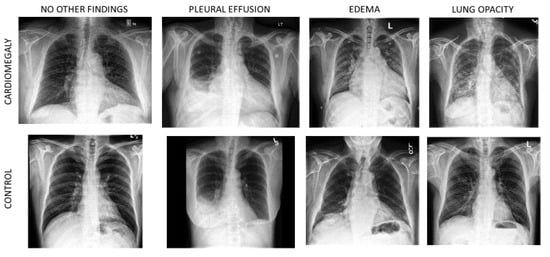

3.4. Grad-CAM++ Analysis

| All | Control | Cardiomegaly | |

|---|---|---|---|

| Number of Patients: | 2436 | 1225 | 1211 |

| Age: | 58.6 ± 17.7 | 54.4 ± 17.2 | 62.9 ± 17.1 *** |

| Gender Male: | 1520 (62%) | 794 (65%) | 726 (59%) * |

| One or Several Other Findings: | 1474 (61%) | 559 (46%) | 915 (75%) *** |

| Enlarged Cardiomediastinum | 293 (12%) | 151 (12%) | 142 (12%) |

| Lung Opacity | 727 (30%) | 266 (22%) | 461 (38%) *** |

| Lung Lesion | 191 (8%) | 91 (7%) | 100 (8%) |

| Edema | 633 (26%) | 133 (11%) | 500 (41%) *** |

| Consolidation | 647 (27%) | 315 (26%) | 332 (27%) |

| Pneumonia | 244 (10%) | 83 (7%) | 161 (13%) *** |

| Atelectasis | 405 (17%) | 139 (11%) | 266 (22%) *** |

| Pneumothorax | 377 (15%) | 215 (18%) | 162 (13%) ** |

| Pleural Effusion | 1054 (43%) | 435 (36%) | 619 (51%) *** |

| Pleural Other | 135 (6%) | 46 (4%) | 89 (7%) *** |

| Fracture | 119 (5%) | 59 (5%) | 60 (5%) |

| Support Devices | 558 (23%) | 226 (18%) | 332 (27%) *** |